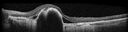

Paclitaxel induced cystoid macular edema - reversed when chemo stopped25 views74 year old retired physician About 2-3 weeks ago there was gradual vision loss in the right eye. The patient was seen by an ophthalmologist who saw macular swelling and injected vabysmo. He has been on chemotherapy (Carbiplatin and Carboxytaxol for 2 cancers - advanced prostrate diagnosed 2019 - has had brain surgery AND squamous lung cancers treated with radiation)

Medical Hx: Prostate cancer (Onset: 2018). Pulmonary and bone cancer metastatic. Brain cancer metastasized from prostate cancer.

Surgical Hx: Right frontal & Frontoparietal Craniotomy (Onset: 2024). Appendectomy. Hemorrhoidectomy. Herniorrhaphy. Prostate. Systemic Meds: Chemotherapy. Radiation. Eligard Every 3 Months 22.5 MG per 0.375 ML Prefilled Syringe. MIRALAX prn. Tums Freshers 500 MG Chewable Tablet. Vitamin D. XGEVA.

VA OD: Dcc20/125+1

VA OS: Dcc20/125-2

TP: OD:12 OS:15Aug 17, 2025